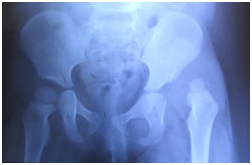

第一次术前